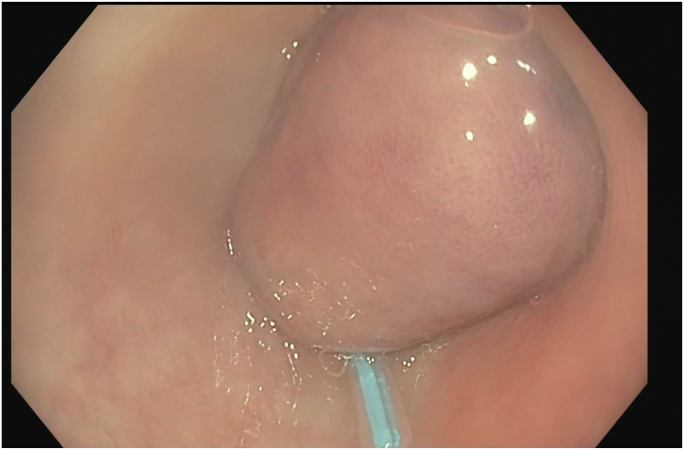

Figure 1.

Large 50-mm sigmoid polypoid mass seen on colonoscopy.